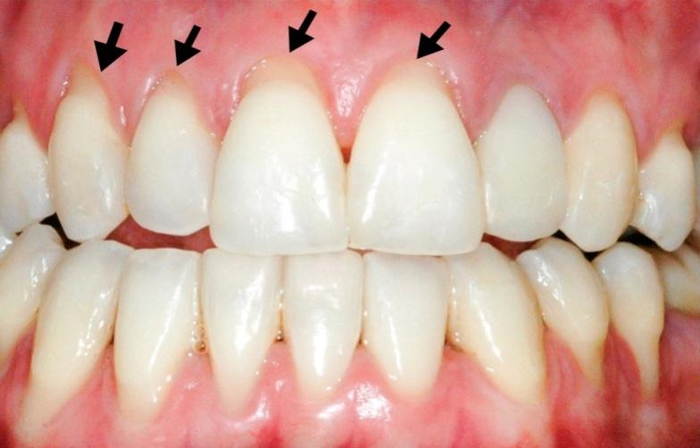

很多人刷牙会认真刷牙面,却很容易忽略牙龈(牙肉)边缘的龈沟。

其实,牙菌斑很容易积聚在这个地方,加重龋齿、牙周炎的风险。

如果平时没清洁到位,软垢、色素这些坏家伙也可能“聚众闹事”,使靠近牙龈部分的牙齿发黄更明显。

长期不清理牙龈沟,还容易形成牙结石,导致我们的牙龈容易发炎,甚至出血。